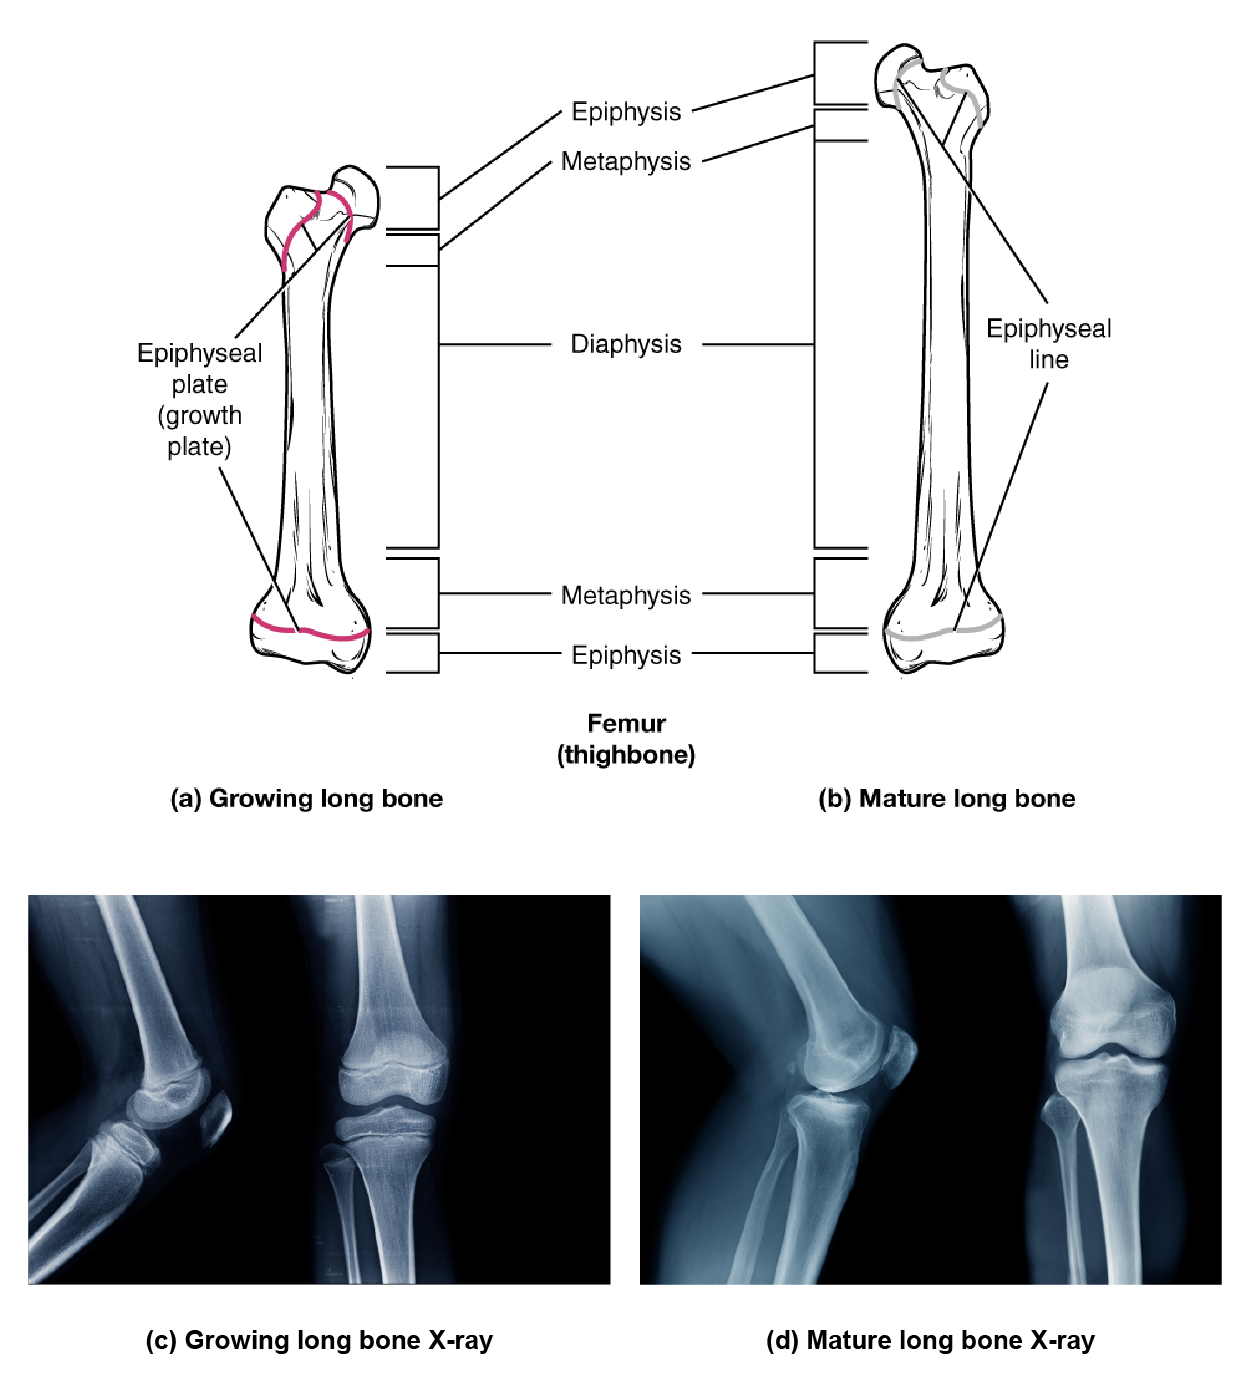

Bones continue to grow in length until early adulthood. The rate of growth is controlled by hormones, which will be discussed later. When the chondrocytes in the epiphyseal plate cease their proliferation and bone replaces all zones of the epiphyseal plate, longitudinal growth stops. The epiphyseal plate then completely converts to bone, becoming the epiphyseal line, a dense region of osseous tissue separating the diaphysis and epiphysis. An X-ray of this region shows the presence of an epiphyseal plate or line and can be used to determine whether a bone is done growing or not as well as its approximate age.

This illustration shows anterior views of a right and left femur. The left femur possesses a growth plate at the border of its distal metaphysis and distal epiphysis. The proximal epiphysis has two growth plates. The first is located below the head of the femur while the second is located below the trochanter, which is the bump on the lateral side of the femur. The right femur has the same plates as the left femur. However, the left femur represents a mature long bone. Here, growth is completed and the epiphyseal plate has degraded to a thin, faint, epiphyseal line. In the lower panel, x-ray images show a growing long bond with dark gaps where the growth plates exist and a mature bone where the same region is bright white bone.

Progression from Epiphyseal Plate to Epiphyseal Line - As a bone matures, the epiphyseal plate progresses to an epiphyseal line. (a) Epiphyseal plates are visible in a growing bone. (b) Epiphyseal lines are the remnants of epiphyseal plates in a mature bone. (c) Epiphyseal plates show up on X-rays as dark gaps in the bone. (d) Epiphyseal lines show up on X-rays as bright bone.